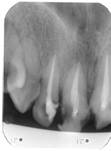

La nivelul lui 12 si 13 se observa obturatia de canal corect executata din punct de vedere radiologic. Clinic se constata obturarea canalelor radiculare cu ciment oxifosfat de zinc si fara con de gutaperca. Pe a doua radiografie se observa dezobturarea corecta a canalelor radiculare pt. realizarea unor DCR-uri.

Radiografii retroalveolare la inceputul si la sfīrsitul tratamentului endodontic